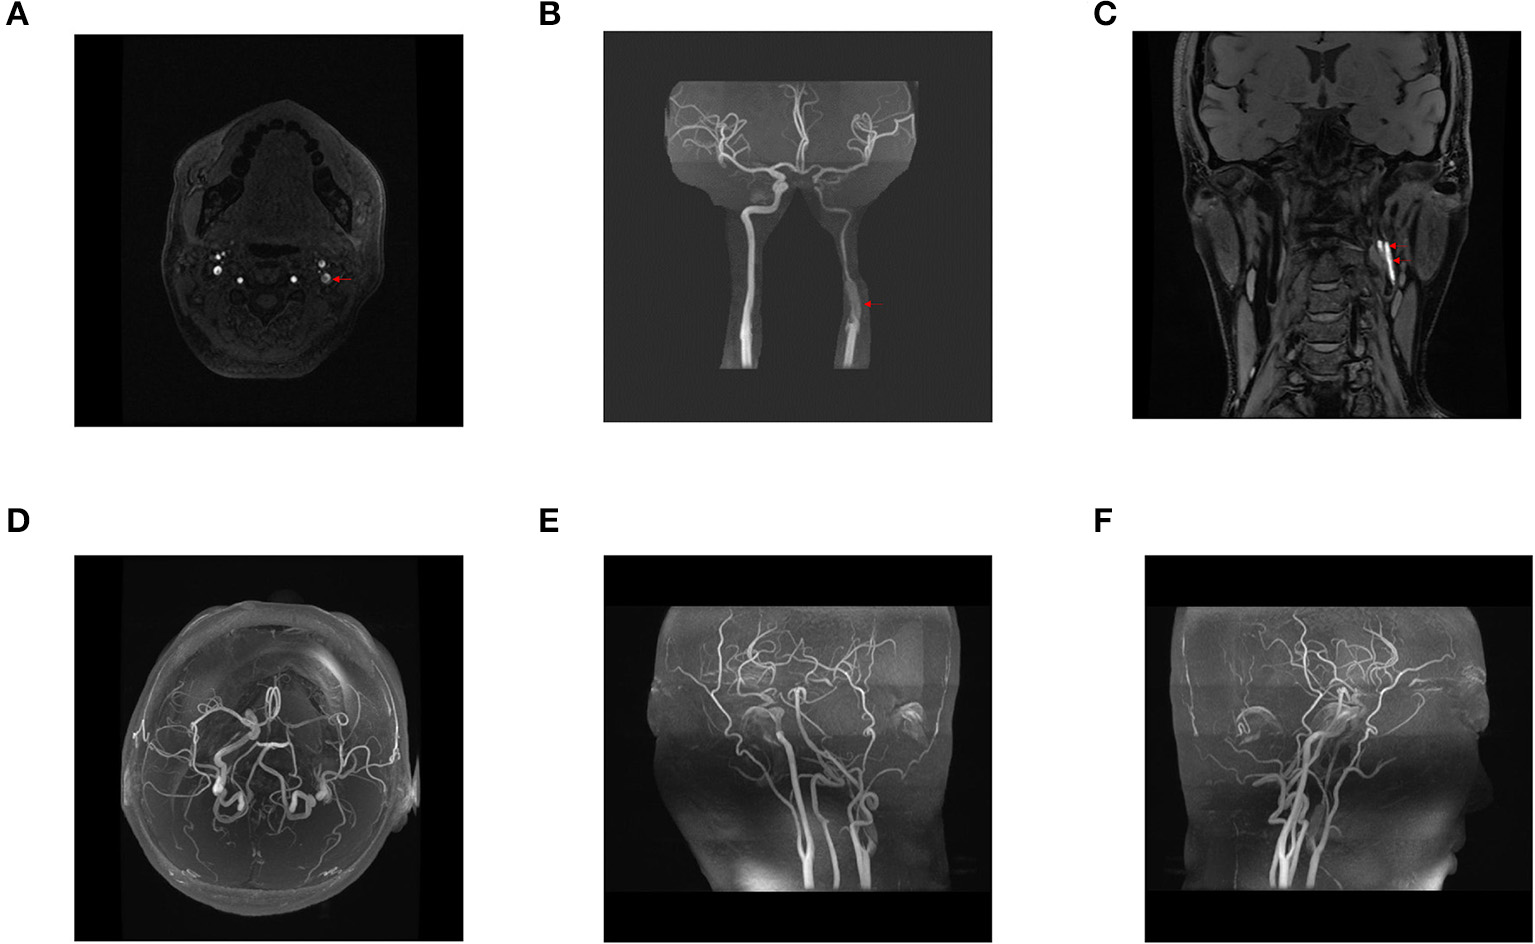

A 41-year-old woman with no risk factors for cardiovascular disease and carotid artery dissection presented with speech difficulties and hemiplegic gait 2 weeks after the 7D HIFU cosmetic procedure for removing necklines. After 7D HIFU treatment, the patient had a constant, throbbing headache (NRS 2–9 points), which gradually spread from the occipital to the temporal area and was slightly alleviated by overextension of the neck. Headache was accompanied by dizziness, amaurosis, nausea, and drowsiness but was not associated with vomiting or tinnitus. Headache was not alleviated by analgesics and gradually aggravated over the past 2 weeks. MRI of the patient's head showed an ischemic stroke in the left parietal lobe, the left temporal lobe, and the left insular lobe. In addition, head and neck magnetic resonance angiography (MRA) and computed tomography angiogram (CTA) revealed dissection and severe stenosis in the left internal carotid artery (Figures 1, 2). Physical examination revealed no specific findings. We consider the damaging heat effect of the 7D HIFU to be the primary trigger of the left internal carotid artery dissection and the severe carotid artery stenosis through overall consideration of the present history, past history, physical examination, and imaging examination of the patient.

Figure 1

Preoperative head and neck magnetic resonance angiography (MRA), three-dimensional reconstruction of head and neck MRA, and blood flow assessment. A dissection at the origin of the left internal carotid artery was observed, and the left internal carotid artery was severely stenosed (A–C). Stenosis at the origin of the left internal carotid artery was associated with an intermural hematoma (C). The right internal carotid, bilateral middle, and anterior cerebral arteries showed no apparent thickening, stenosis, or signal loss (D–F). The bilateral vertebral, basilar, posterior cerebral arteries and their branches were clearly displayed, with no obvious thickening and stenosis (E,F). The bilateral posterior communicating arteries were found opened (D). Blood flow assessment: arterial spin labeling (ASL) revealed a basic symmetry of cerebral blood flow in both cerebral hemispheres.